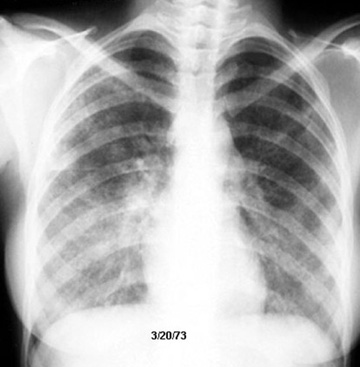

Sarcoidosis Spontaneous regression

Pulmonary function improved along with radiological clearance.